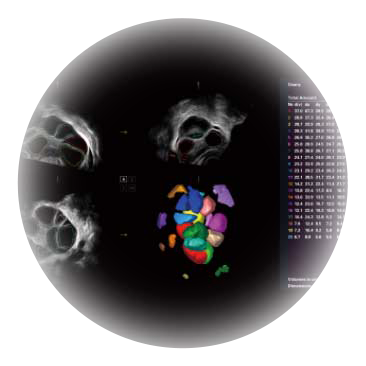

卵泡结构的自动识别和测量,可显示多组测量数据。